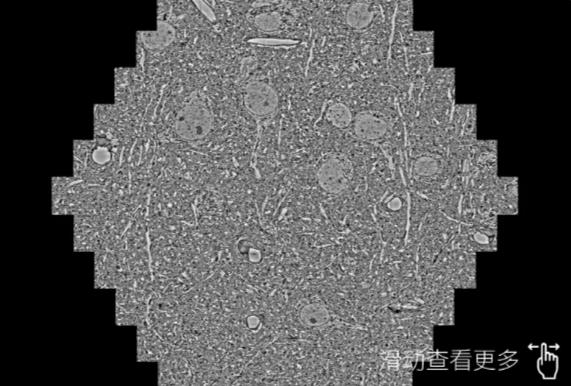

鼠脑切片。左图使用渝中蔡司渝中扫描电镜MultiSEM706对165μmx143pm面积区域成像,耗时仅需1.5秒。右图为鼠脑切片中30μm区域放大效果。样品由芝加哥大学B.Kasthuri提供。

使用蔡司高速渝中扫描电镜MultiSEM对1mm²人脑皮层组织进行高分辨成像,并对其中的各种细胞结构进行三维重构分析。左图展示了2x3mm²组织平面中锥体神经元的三维重构效果。右图显示了局部体积神经元三维重构。图像由哈佛大学chtman实验室提供,渲染图由D. Berger 制作。